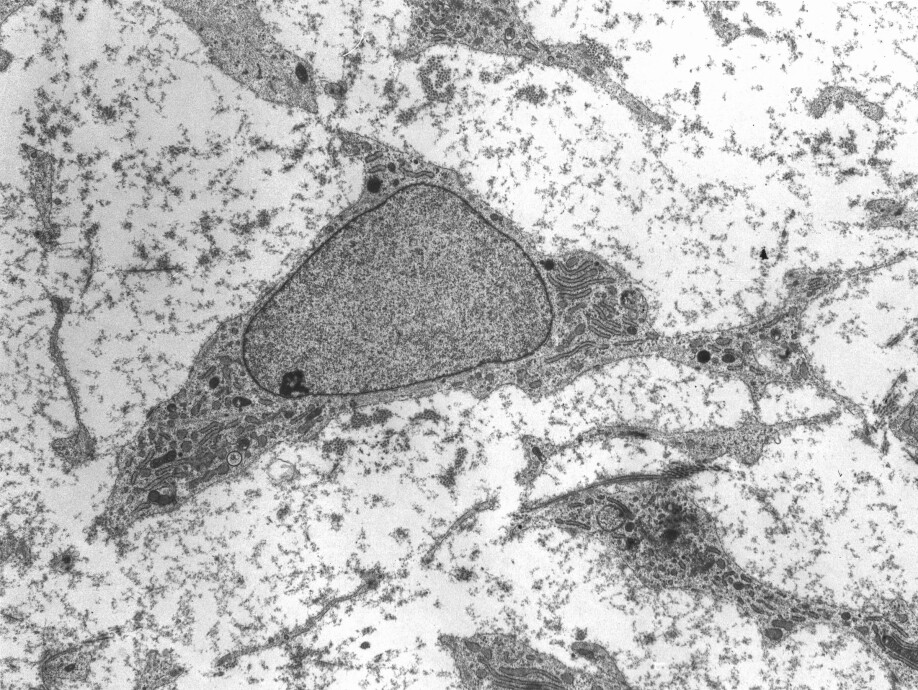

The student researchers are growing something called cardiac organoids. These are heart cells that together form structures like a heart in a living human being.

“The advantage of cardiac organoids is that they’re similar to the heart tissue in humans. It makes it easier for us to study and understand how a human heart works, and we can study the course of a disease. It’s also conceivable that with this knowledge we’ll be able to find treatments for various heart diseases,” says Solvang.